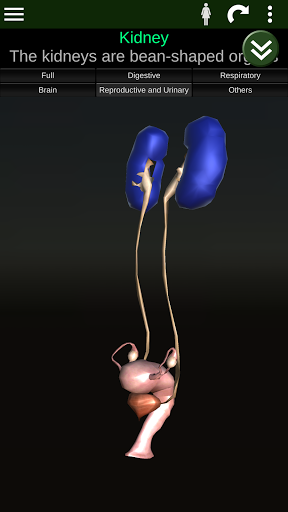

Показує 3D анатомічну модель основні органи людського тіла та опис кожного з них.

* Репродуктивна система, яка включає чоловічі та жіночі репродуктивні органи.

* Описи кожного органу.